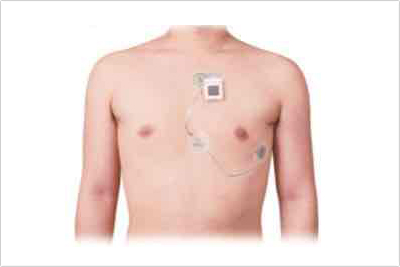

24時間小さな心電図をつけていただき、不整脈が出ているかなどを調べます。2022年に最新式のものに変更しました。 シャワーを浴びても大丈夫です。